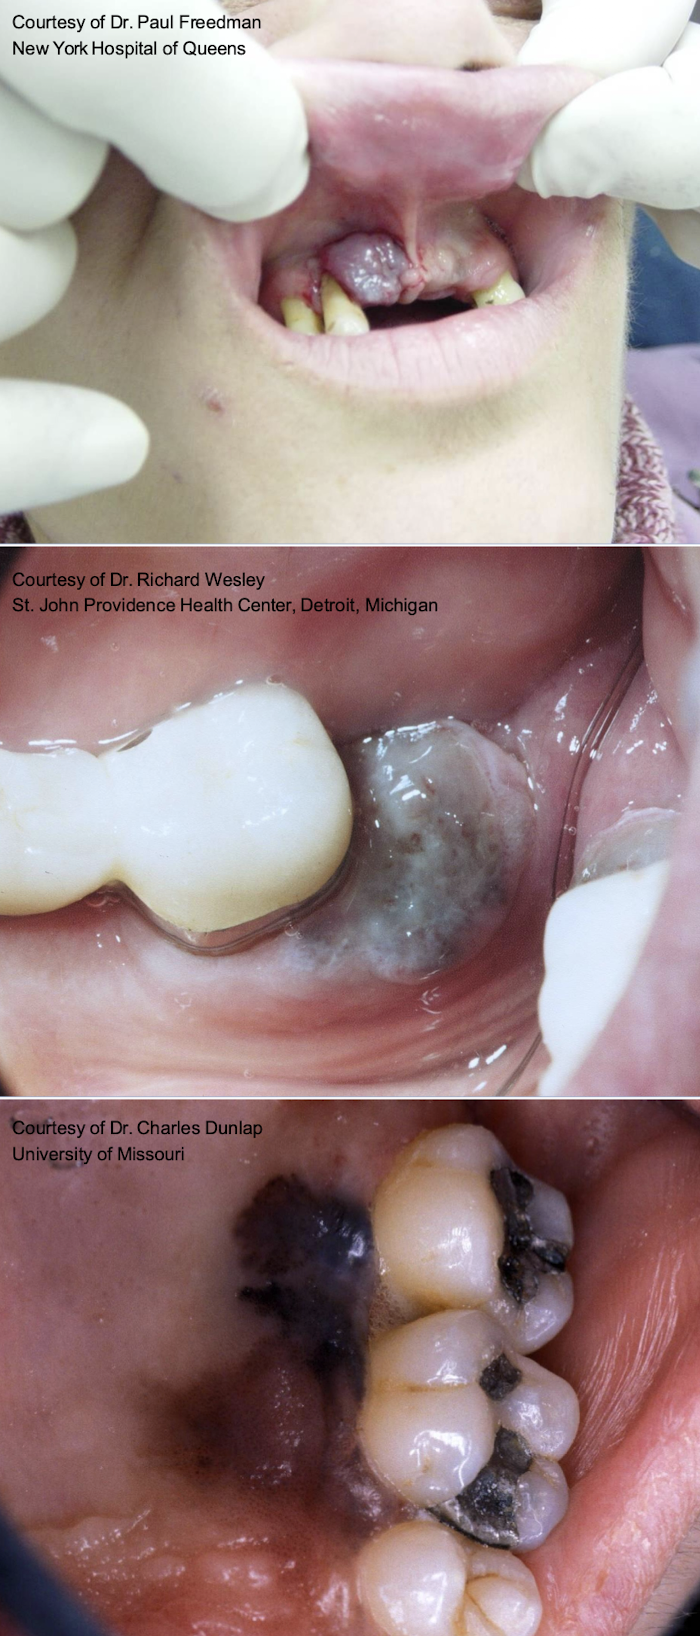

Krompecher in 1918 as a congenital "melanocarcinoma”

90% in head and neck and within the first 6 months of life

Male predilection (1.5:1), 60% on the palatal mucosa

Brownish-red mass of alveolar mucosa

High levels of vanillylmandelic acid in urine

BRAF V600E mutation identified in some cases (targeted therapies yay!)

surgically excised

MNTI

surgical resection (~20% recurrence rate; some intentionally left to be removed later)

which premalignant/malignant melanin-associated pigmented lesion?

More prevalent in African Americans and Japanese

Arise de novo

7th decade, slight male predilection

Palatal mucosa, maxillary gingiva (>70%)

Breslow and Clark criteria (skin criteria) do not correlate with clinical behavior/prognosis

can be heterogenous or homogenous

oral melanomas

heterogenous oral melanoma

oral melanoma